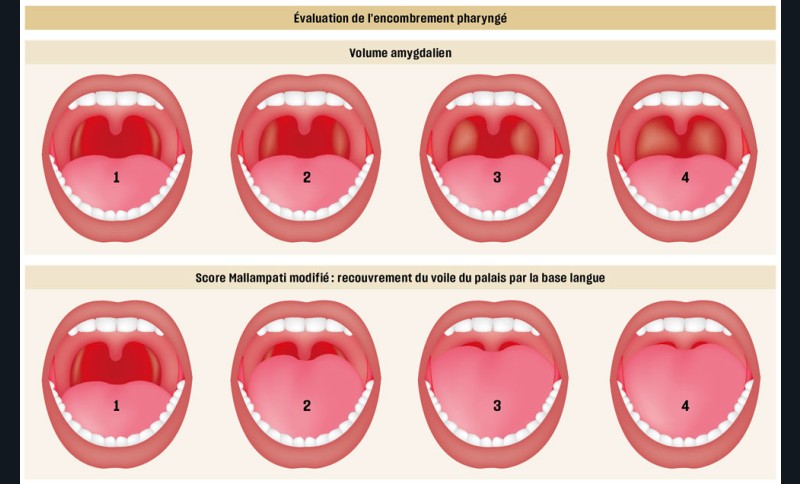

– Hypertrophie amygdalienne/adénoïdienne – Rétromaxillie, rétromandibulie – Palais étroit, haut – Face longue – Macroglossie ou bords de langue indentés – Position de langue anormale (score de Mallampati) – Frein de langue court – Obstruction nasale – Obésité |

On évalue également la forme générale des arcades dentaires, les signes d’encombrement, l’occlusion dans les trois dimensions de l’espace ainsi que la posture et la mobilité linguale. Une classe II dentaire marquée, une constriction du maxillaire (endoalvéolie ou endognathie associées ou non à un articulé croisé postérieur) ainsi qu’une béance antérieure sont des signes d’appels de Sahos [8] (fig. 7). Une triade intra-orale évocatrice est souvent présente chez ces enfants : palais étroit et profond, troubles de la posture linguale (macroglossie, frein lingual court, etc.) et Hypertrophie amygdalienne (HTA) [5].

La persistance du Sahos peut être expliquée par la présence de certaines comorbidités (obésité, rhinite allergique, asthme), par la sévérité du diagnostic initial ou encore par la présence d’une dysmorphose cranio-faciale [41]. L’hypertrophie des cornets nasaux, une déviation de la cloison nasale, un score de Mallampati à 3 ou 4 ou le mode de vie sont aussi des facteurs explicatifs [8-42-43].